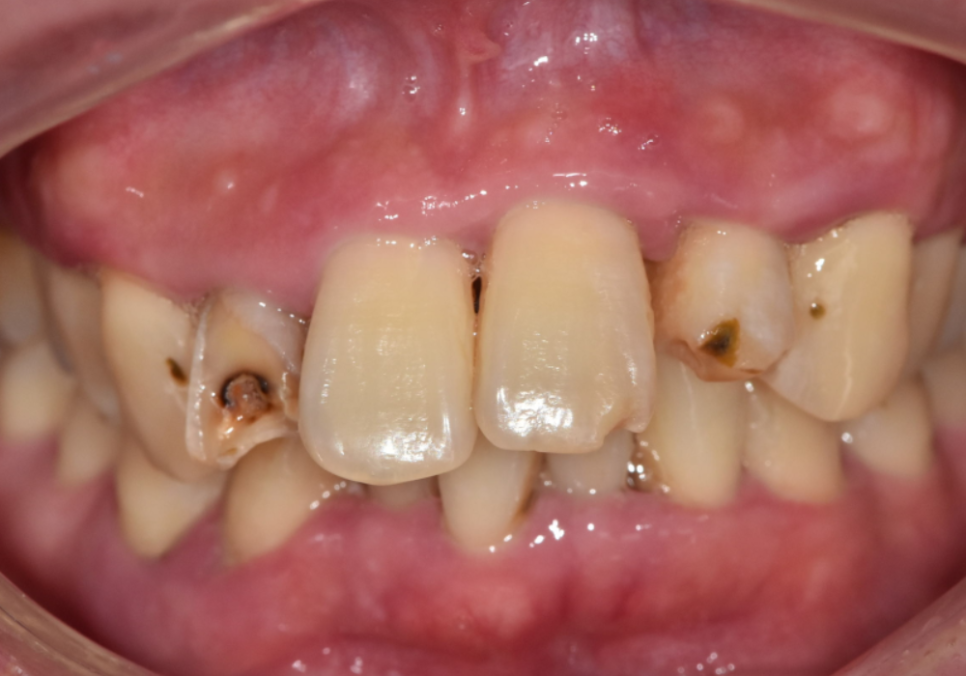

입안을 자세히 살펴보니

치료가 필요한 치아가 총 5군데였습니다.

250424

앞니, 치아 상태

강동구 앞니 충치

치아 겉면에 충치가 살짝 진행된 상태

음식을 씹다 살짝 파절(깨짐)된 상태

충치 범위가 넓고 마모까지 심한 상태

이 중 가장 문제는

오른쪽 옆 앞니(#12)였습니다.

육안으로만 봤을 때는

치아 머리 부분이 꽤 남아 있어서

'이것도 크라운으로 씌우면 되겠지' 싶었지만,

손으로 살짝 건드리기만 해도

힘없이 흔들거리는 불안한 상태였어요.